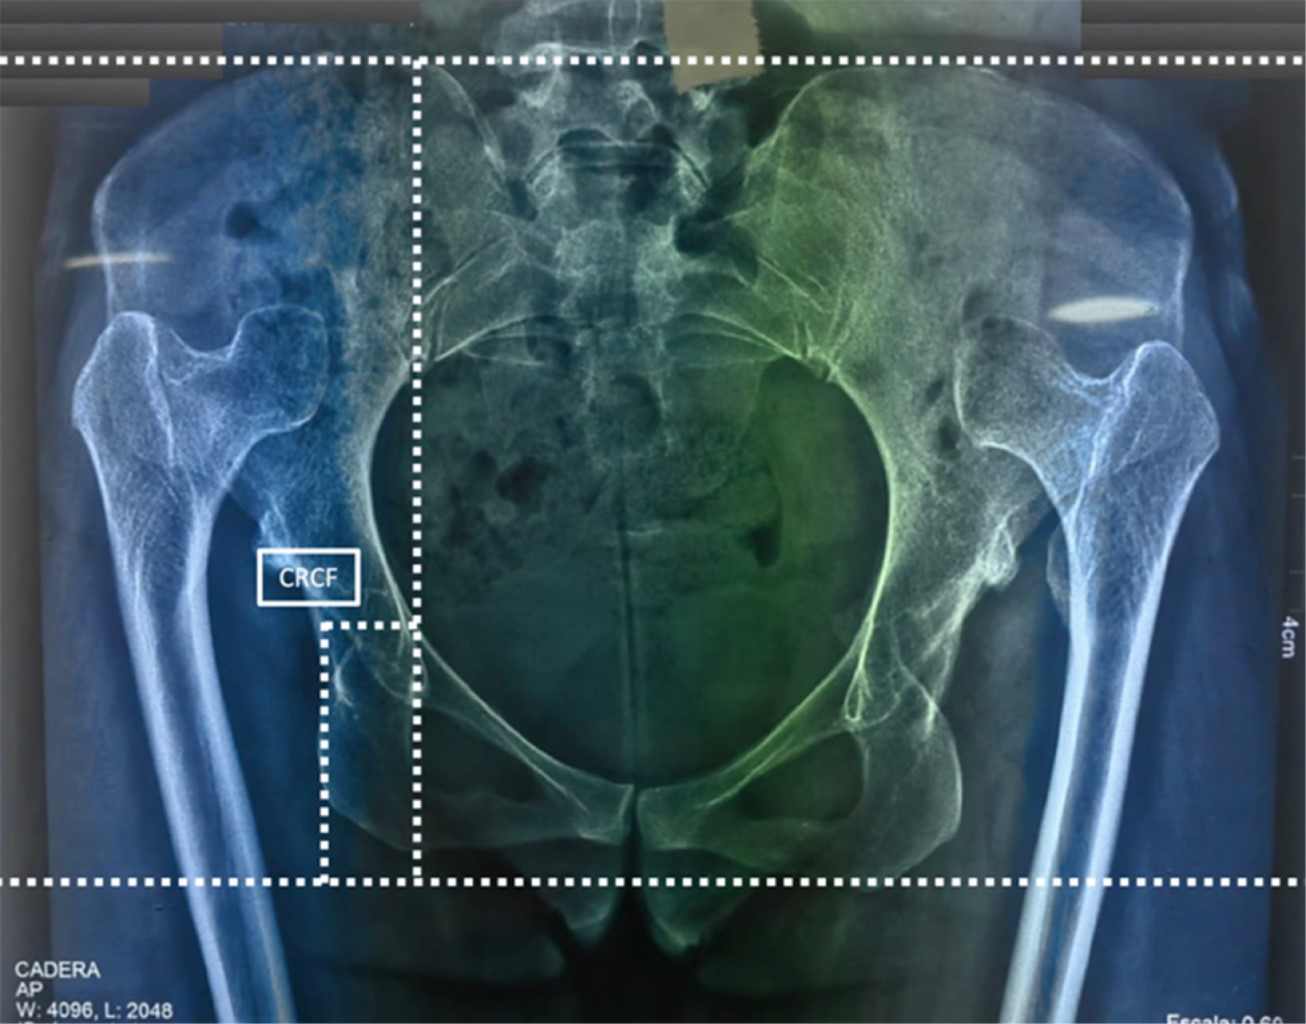

Esta presentación tiene como objetivo describir el caso clínico de una paciente femenina de 29 años y la técnica quirúrgica empleada en la ATC asociada a osteotomía de acortamiento supracondílea en luxación de cadera inveterada Crowe 4 (Figura 1), utilizando implantes no cementados copa TrinityMR (Corin) y vástago MiniHipMR (Corin) con un par de fricción cerámica-polietileno con fijación distal (placa LC-LCP 4 orificios).

Al tratarse de una luxación inveterada bilateral Crowe 4, el objetivo de esta cirugía es restaurar el centro de rotación de la cabeza femoral (CRCF) nativo del acetábulo, por lo que se realizan mediciones preoperatorias para obtener dicho centro, tomando como referencia la línea interilíaca e interisquiática (Figura 1), istmo femoral y metáfisis para tomar en consideración el tamaño de los implantes, como primera instancia se propuso realizar osteotomía femoral supracondílea, con la finalidad de utilizar un vástago corto de apoyo metafisario.

Figura 1